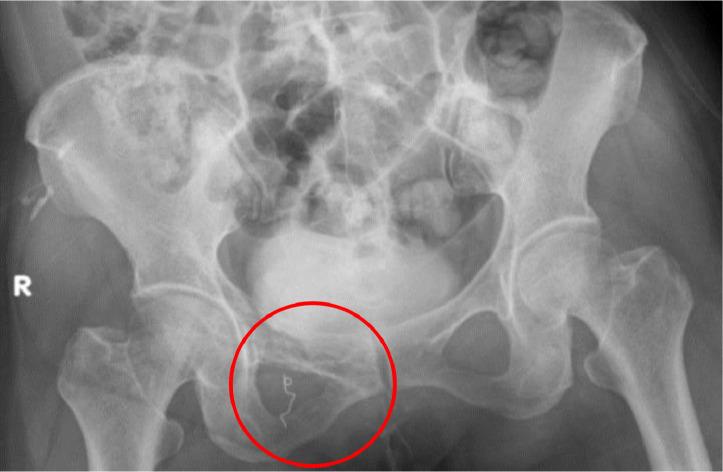

经动脉注射阿霉素洗脱微球栓塞术治疗耻骨区硬纤维瘤病

Transarterial doxorubicin-eluting beads embolization for the treatment of desmoid fibromatosis in the pubic region.

Desmoid fibromatosis (DFs) is rare, low-grade neoplasm. Although it poses no risk of metastasis, DFs exhibits a range of clinical manifestations characterized by local infiltrative growth tendencies and a propensity for recurrence. Despite its nonmalignant nature, DFs can be highly debilitating and occasionally life-threatening, causing severe pain and functional limitations. Traditionally, surgery served as the conventional primary treatment approach; nevertheless, a recent shift in paradigm towards a more conservative management has emerged, accompanied by efforts to standardize the strategy among clinicians. Systemic doxorubicin has been demonstrated to be effective in treating DFs; however, it carries potential risks of adverse effects on the cardiovascular, digestive, and hematologic systems. The novel intravascular intervention employing drug-eluting beads loaded with doxorubicin represents an effective treatment for DFs, optimizing drug delivery to the target lesion and reducing systemic toxicity. In this article, we present a rare case of DFs in the right pubic region treated with transarterial doxorubicin-eluting beads embolization.

摘要

韧带样型纤维瘤病(DFs)是一种罕见的低度恶性肿瘤。尽管它没有转移风险,但DFs表现出一系列临床表现,其特征为局部浸润性生长倾向和复发倾向。尽管DFs本质上并非恶性,但它可能极具致残性,偶尔还会危及生命,导致严重疼痛和功能受限。传统上,手术是常规的主要治疗方法;然而,最近出现了向更保守治疗模式的转变,同时临床医生也在努力使治疗策略标准化。已证明全身使用阿霉素对治疗DFs有效;然而,它对心血管、消化和血液系统存在潜在的不良反应风险。采用载有阿霉素的药物洗脱微球的新型血管内介入治疗是DFs的一种有效治疗方法,可优化药物向靶病变的递送并降低全身毒性。在本文中,我们介绍了一例经动脉阿霉素洗脱微球栓塞治疗的右侧耻骨区罕见DFs病例。